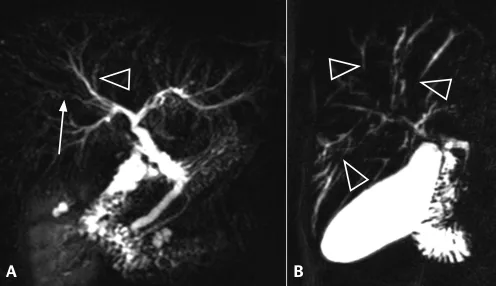

Figure 16. Exemple d’exploration par bili-IRM d’une volumineuse TIPMP de la tête du pancréas (têtes de flèches). Il s’y associe d’autres localisations corporéo-caudales de petite taille, et une augmentation de calibre du canal pancréatique principal